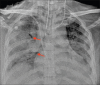

Results: 756 RT-PCR confirmed COVID-19 patients were included in our study who had initial CXR. 510 (67.46%) of our patients with positive initial RT-PCR showed abnormal baseline CXR. The abnormal findings were described as haziness akin to ground glass opacities (GGO) on CT, peripheral opacities, patchy parenchymal opacities and consolidation. Peripheral opacities and lower zone distribution were the commonest pattern of CXR abnormalities with bilateral involvement. The severity of findings on serial CXR and radiographic regression was studied along with follow-up to assess response to treatment. Forty-six patients showed features of acute lung injury (ALI). Complications and new CXR findings were reported for patients who were given ventilator support.